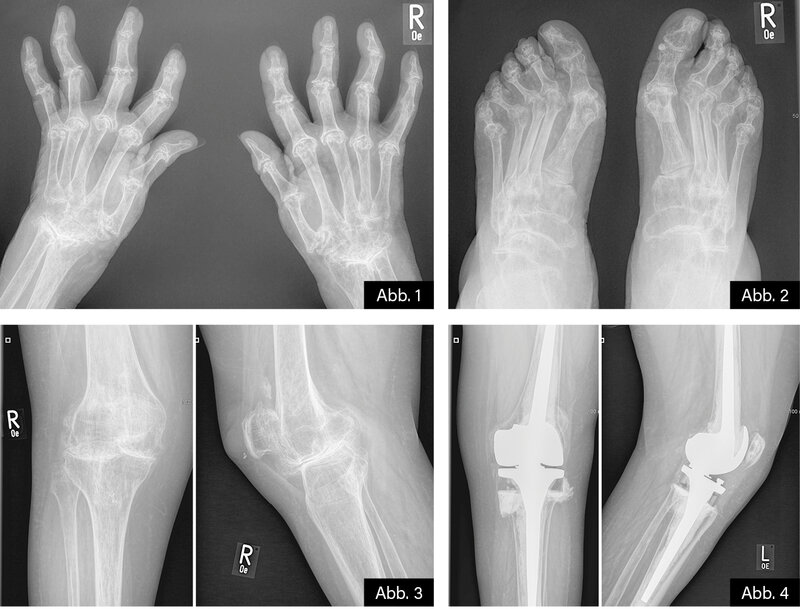

BILDGEBENDE DIAGNOSTIK: Röntgen (s. u.)

DIAGNOSE: Langjährige destruierende seropositive RA

Konventionelle Röntgenaufnahmen bleiben dennoch Standard zur Verlaufskontrolle, da sie typische destruktive Veränderungen wie gelenknahe Usuren, Destruktionen, Fehlstellungen und Osteoporose nachweisen können. Radiologische Veränderungen dokumentieren das Fortschreiten der destruktiven Prozesse und sind wichtig für die Therapieentscheidung und Prognoseabschätzung.